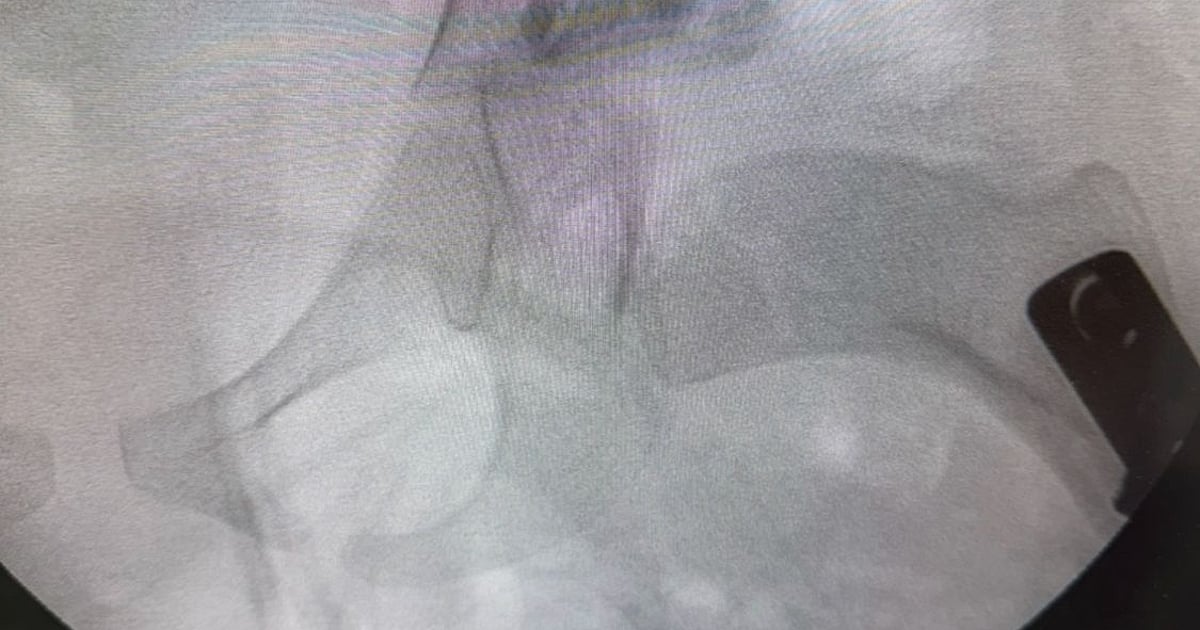

في إنجاز طبي لافت، نجح فريق طبي من قسم جراحة العظام في مستشفى المانع بالخبر، بقيادة استشاري جراحة عظام الأطفال الدكتور إبراهيم البراهيم، في إجراء عملية دقيقة لطفلة تبلغ من العمر أربع سنوات كانت تعاني من خلع ولادي مزدوج في مفصل الورك وتشوه في رأس عظمة الفخذ مع انحراف في عنق العظمة بالجهتين.